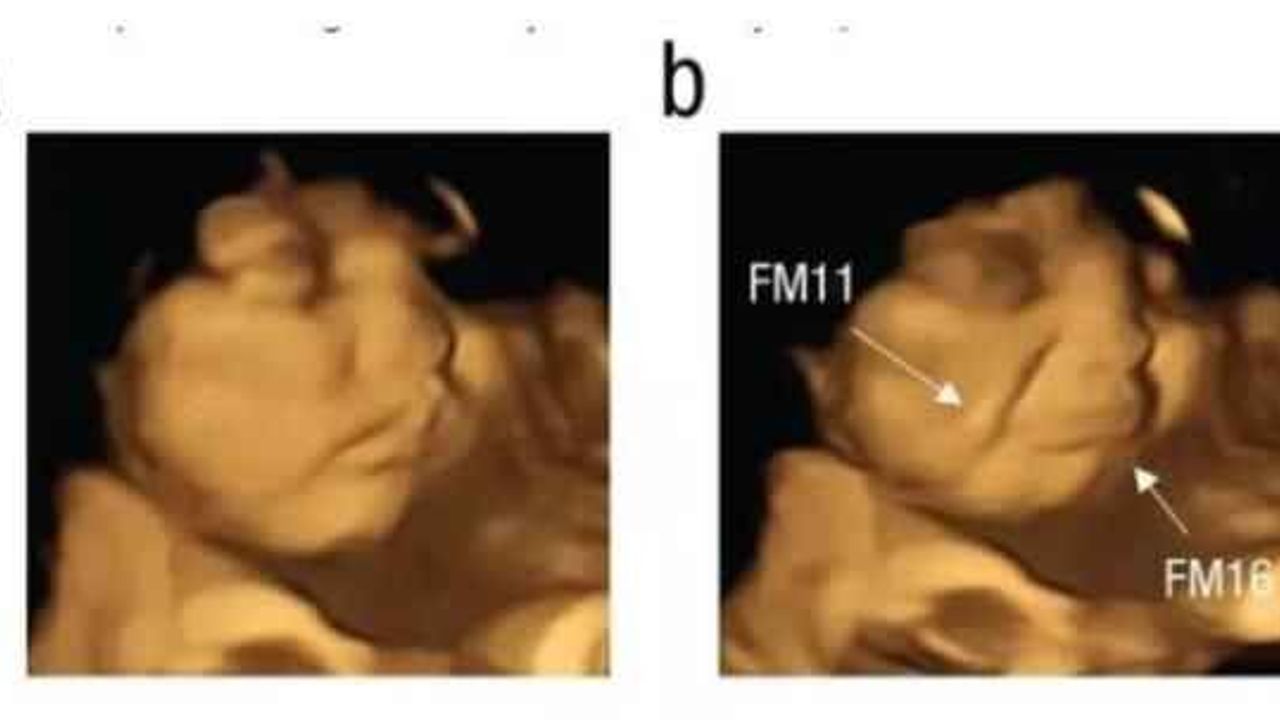

Independent'ın haberine göre, Durham Üniversitesi'nden bilim insanları, fetüslerin farklı tatlara tepki verip vermediğini görmek için 4D ultrason taramaları kullandı. Durham Üniversitesi Psikoloji Bölümü'den Beyza Üstün'ün liderliğindeki araştırma ekibi, fetüslerin belirli tatları ayırt edip edemediğini görmek için 18-40 yaşları arasındaki 70 hamileyi iki gruba ayırıp ultrason görüntülerini inceledi.

Psychological Journal'da yayımlanan çalışmada araştırmacılar, annenin diyetinden gelen tat ve koku bileşimli aromaların 32 ila 36'ncı gebelik haftalarında amniyotik sıvıda hissedildiğini tespit etti.

LAHANA TATINI ALINCA YÜZÜNÜ EKŞİTTİ

Çalışmaya katılan anne adaylarının raporlama öncesinde herhangi bir gıda tüketmemesi talep edildi. Çalışma kapsamında bir grup anne toz havuç tüketirken diğer grup ise lahana tozu yedi. Lahana tozuna maruz kalan bebeğin, yüzünü ekşittiği görüldü. Fetüslerin reaksiyonunu doğumdan önce gösteren ilk çalışma olarak nitelendirilirken makalede imzası olan Dr. Benoist Schaal da sonuçların bu kadar net olmasını şaşırtıcı olarak değerlendirdi.